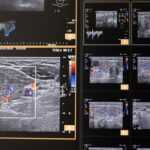

Color Doppler je temeljen na ultrazvučnoj tehnologiji koja pomoću Doppler-ovog efekta procjenjuje prokrvljenost cijele štitnjače i čvorova u štitnjači, kao i limfnih čvorova vrata. Pomoću color Dopplera računamo brzine protoka kroz krvne žile koje hrane štitnjaču, čime dobivamo važne hemodinamske parametre. Na temelju ovih pokazatelja donosimo važne dijagnostičke zaključke, te efikasno pratimo efekte liječenja štitnjače.

U sklopu Centra za štitnjaču Poliklinike Lacić nabavljen je najnoviji američki ultrazvučni aparat sa color Dopplerom Philips Affiniti 70, koji je opremljen jedinstvenim „PureWave“ ultrazvučnim sondama. Tehnologija izrade tzv. „single crystal“ ili „PureWave“ ultrazvučnih sondi omogućuje duboku penetraciju što omogućuje bolju vizualizaciju štitnjače i svih struktura vrata. Philips Affiniti 70 ultrazvučni sustav je jedini sustav u klasi koji može koristiti „single crystal“ ili „PureWave“ tehnologiju. Čisti, uniformni „PureWave“ kristali imaju 85% bolju učinkovitost prilikom emitiranja i primanja ultrazvučnih zraka nego klasični piezoelektrični materijali. Ova izuzetna tehnologija omogućuje naprednu penetraciju uz izvrsnu rezoluciju u dubljim dijelovima slike, čime se postiže vrhunski prikaz štitnjače i svih struktura vrata. Time se omogućuje još točnije mjerenje svih morfoloških kao i hemodinamskih parametara. Na taj način smo u mogućnosti još ranije otkrivati bolesti štitnjače a samim time ih onda i bolje liječiti.